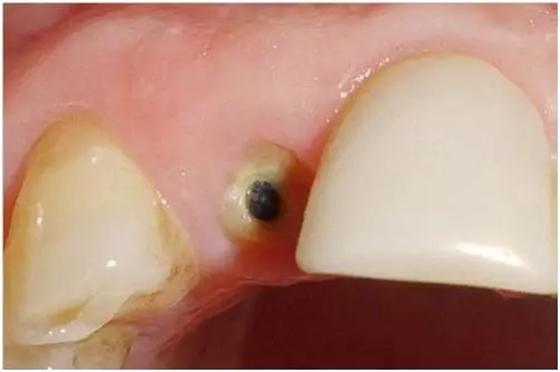

圖1:外傷9天后的臨床檢查:12牙牙冠在釉牙骨質(zhì)界水平處折斷。部分折斷面被牙齦覆蓋,可以看到中央有折斷的金屬根樁(鈦)。11和21牙由復合樹脂貼面修復,22牙由金屬烤瓷冠修復。

圖3:外傷9天后的臨床檢查:12牙牙冠在釉牙骨質(zhì)界水平處折斷。部分折斷面被牙齦覆蓋,可以看到中央有折斷的金屬根樁(鈦)。